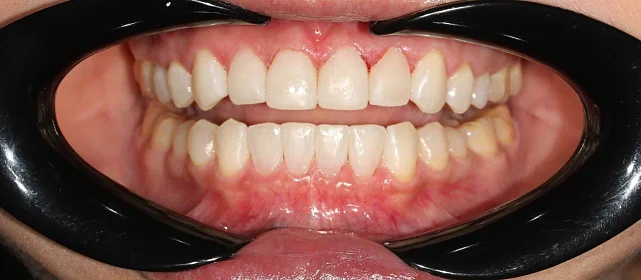

Результат

Зубы выровнены, смыкание нормализовано. Установлены несъёмные ретейнеры на обе челюсти. Пациент направлен к ортопеду.

Решение: Поставили элайнеры Invisalign на обе челюсти. Лечение заняло 4 года — случай потребовал нескольких этапов коррекции, каждый из которых последовательно приближал зубы к нужному положению. Капы менялись каждые 1–2 недели, контрольные визиты — для отслеживания прогресса и выдачи новых наборов. Зубы встали на место, смыкание пришло в норму. Зафиксировали ретейнеры на обе челюсти, пациент направлен к ортопеду для завершающего этапа.

Случай потребовал нескольких последовательных этапов коррекции. Invisalign позволяет дозаказывать капы в рамках лечения, и здесь это понадобилось — каждый следующий этап доводил положение зубов точнее. Результат достигнут, прикус стабилен, ретейнеры на месте. Пациента направила к ортопеду.